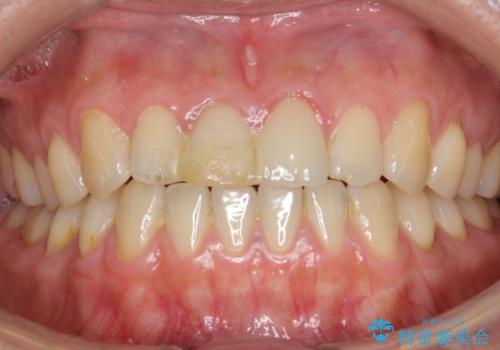

天然歯と見紛うほどの自然な仕上がりに大変喜んで頂けました。

隣在歯を模倣した表面性状・繊細なグラデーション・透明感による再現性の高いセラミッククラウンは、熟練した技工士さんの技術の賜物です。

ジルコニアクラウン エクセレント